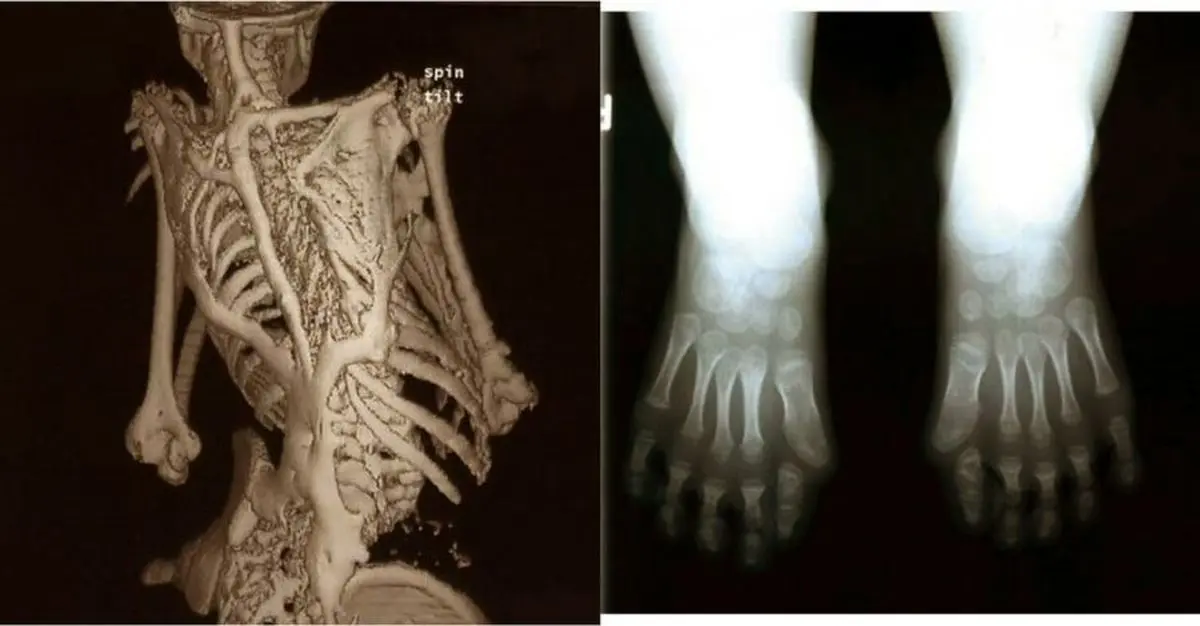

سندرم انسان سنگی یا Fibrodysplasia ossificans progressiva

این بیماری یک بیماری بافت همبند بسیار نادر است که در آن ماهیچه ها، تاندون ها و بافت همبند به آرامی به استخوان تبدیل می‌شوند و در نهایت بیمار کاملاً از نظر حرکتی ناتوان می‌شود. این بیماری شدید و ناتوان کننده بدون درمان و معالجه است.